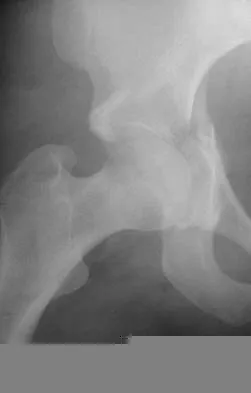

A 21-year-old collegiate female cross-country athlete reports right hip pain that begins about 12 miles into a run, followed by pain resolution when she discontinues running. However, each time she tries to resume a running program, she experiences recurrence of pain deep in the anterior groin. A plain radiograph and MRI scan are shown in Figures 8a and 8b. Management should consist of

Explanation

The history is consistent with a stress fracture. Findings on the plain radiograph are marginal, but the MRI scan shows evidence of stress reaction in the medial neck of the femur (compression side). A lesion on the compression side is not normally at risk for displacement and usually can be managed nonsurgically. A bone scan would further identify the lesion but is not necessary. A skeletal survey and chest radiograph are used in staging a tumor. Radioisotope injection and guided biopsy are sometimes used for osteoid osteomas. Boden BP, Osbahr DC: High-risk stress fractures: Evaluation and treatment. J Am Acad Orthop Surg 2000;8:344-353.